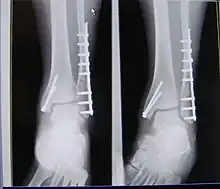

| X-ray of trimalleolar fracture repair before and after ORIF surgery | |

Surgical repair using open reduction and internal fixation is generally required, and because there is no lateral restraint of the foot, the ankle cannot bear any weight while the bone knits. This typically takes six weeks in an otherwise healthy person, but can take as much as twelve weeks. Non-surgical treatment may sometimes be considered in cases where the patient has significant health problems or where the risk of surgery may be too great.[1]